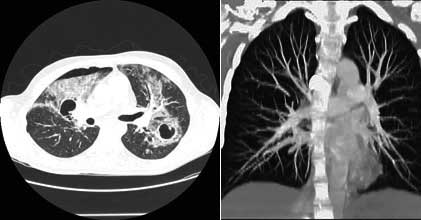

CT screening (rano otkrivanje) karcinoma pluća

Karcinom pluća je najčešći karcinom kod muškaraca,  pa se ranom otkrivanju te bolesti pridaje velika važnost. Uvođenje višeslojnog CT-a (MSCT) u kliničku praksu omogućilo je i screening (rano otkrivanje) karcinoma pluća. Pregled je namijenjen onima koji su visokog rizika za karcinom pluća i omogućava otkrivanje izrazito malih čvorova u plućima, koji mogu biti prisutni, a da nisu vidljivi na standardnom rtg snimku pluća. Rano otkrivanje ovih promjena može dramatično poboljšati uspješnost liječenja karcinoma pluća.

CT screening pluća se preporučuje uraditi pušačima starijim od 60g, a čiji pakovanje-godine index je veći od 10 (pakovanje-godine index se dobije tako što se pomnoži broj godina pušenja sa brojem kutija cigareta koje se ispuše svaki dan: preko 80% karcinoma pluća se dijagnostikuje u ljudi starijih od 60g). Drugi kandidati za pregled su pacijenti starosti 50-60g, koji imaju pakovanje-godine index 20-30 ili s drugim riziko-faktorima kao što je izlaganje azbestu ili hronična opstruktivna bolest pluća.

Šta mogu očekivati od rezultata testa?

Ako je screening CT uredan dalje ispitivanje nije potrebno.

Ako se nađe čvor u plućima, može biti potrebno uraditi detaljniji-dijagnostički CT pluća, s kontrastom. Često se za čvorove koji su nadjeni pri preventivnom pregledu ispostavi da su granulomi ili ožiljci kada se uradi detaljniji/dijagnostički CT pluca ili se radi o čvorovima benignih karakteristika, koji se potom prate u određjenim periodima da bi se bilo sigurno da se radi o zaista benignoj promjeni.